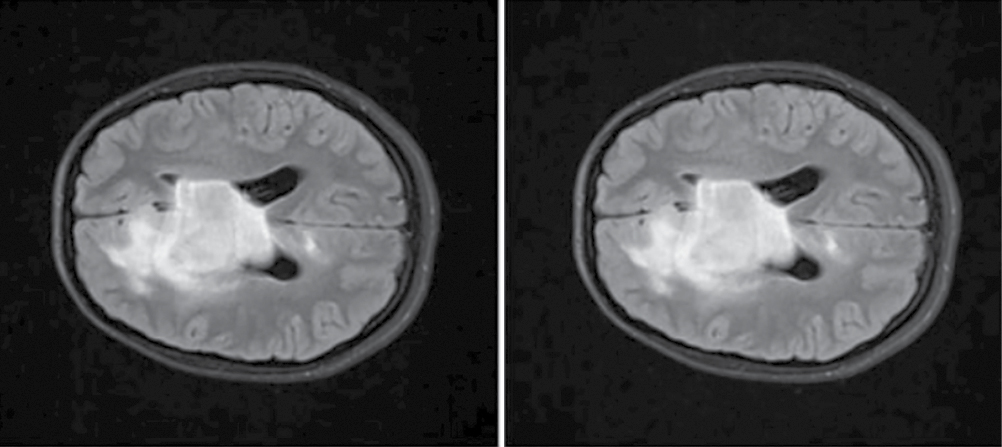

At the previous study stage, we found that the majority of the radiomic predictors characterize ROI heterogeneity by gray level intensity of the voxels. Hence, the higher performance of the model built using the method of the current study stage can be associated with the contrast adjustment. Gamma (γ) value adjusts the contrast as a function: γ < 1 reduces contrast, and γ > 1 augments contrast. At the current study stage, γ was > 0.9, which means that the image contrast was slightly reduced (Fig. 5).

Fig. 5. Diffuse glioma (Т2-FLAIR, ах).

A — raw data; B — AdjustContrast transformed (γ = 0.9).

AdjustContrast is a crucial preprocessing technique used, for example, for computer vision tasks. Contrast adjustment improves the overall sharpness of the image, thereby enhancing the differentiation of its structural elements. This tool is primarily used for low-contrast images, where details are challenging to discern due to the insufficient difference between relatively light and dark regions 3.

The obtained result indicates that the preprocessing of source data from routine MRI based on contrast adjustment significantly improves the predictive performance of the developed model by reliably highlighting the key areas of altered MR signal, which is essential for the qualitative analysis of the MR image (see Table 2). Adjustment, almost imperceptible to the human eye, increased the model predictive performance by 17.5% compared with the model based on the raw data. Thus, γ-correction is not only critical for high-quality presentation of images and videos in different media formats (which is important considering the human-dependent perception of the image) but also a promising tool for standardization of raw medical imaging data preprocessing. However, we noticed slightly pronounced but significantly higher effectiveness of other normalization methods, which apply averaging over the signal amplitudes or bring them to a predefined range, for instance, the ScaleIntensity transform, which demonstrated the highest AUC score.